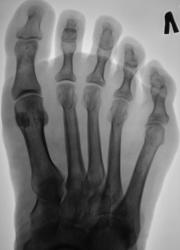

Катенёв Валенти... Дата публикации 25.05.2009, 19:02 Пациентка направлена хирургом в рентгеновский кабинет для рентгенографии стопы с целью "фиксации" процесса заживления (консолидации) косого перелома проксимальной фаланги 5 пальца левой стопы. Ваше мнение коллеги? Пнд, 25/05/2009 - 22:20 #1 OPEXOB Не на сайте Был на сайте: 9 лет 11 месяцев назад Зарегистрирован: 26.07.2008 - 10:02 Публикации: 280 Добавлю: перелом "внутрисуставной", "дистального эпифиза" и оскольчатый.

Добавлю: перелом "внутрисуставной", "дистального эпифиза" и оскольчатый.